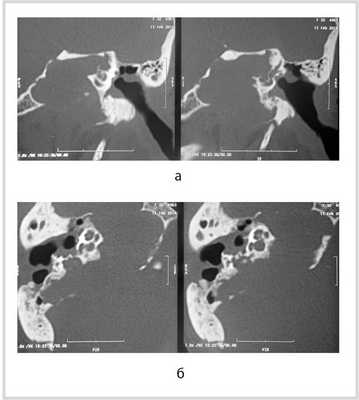

![]()

Рис. 1. КТ височных костей пациентки М. а — коронарная проекция: деструктивная полость в пирамиде височной кости, заполненная субстратом неоднородной плотности, капсула лабиринта значительно разрушена на уровне базального и апикального завитков улитки, латерального и верхнего полукружных каналов; б — аксиальная проекция: деструктивная полость с разрушением задней грани пирамиды, передневерхней и нижней поверхности.

По результатам МРТ головного мозга правая пирамида височной кости деформирована, увеличена в объеме, выполнена субстратом размером до 5,5—2,8—3 см, распространяющимся на область внутреннего слухового прохода, заднего полукружного канала, медиальные отделы барабанной полости, сосцевидный отросток. Описанный субстрат изо-гипоинтенсивен в режиме Т1, гиперинтенсивен — в Т2 и non-EPI DWI (рис. 2). Заключение: признаки рецидива холестеатомы с деструктивными изменениями структур внутреннего и среднего уха на фоне хронических воспалительных изменений.

Рис. 2. Магнитно-резонансная томография головного мозга пациентки М. Деформированная, увеличенная в объеме пирамида височной кости выполнена мягкотканым субстратом.